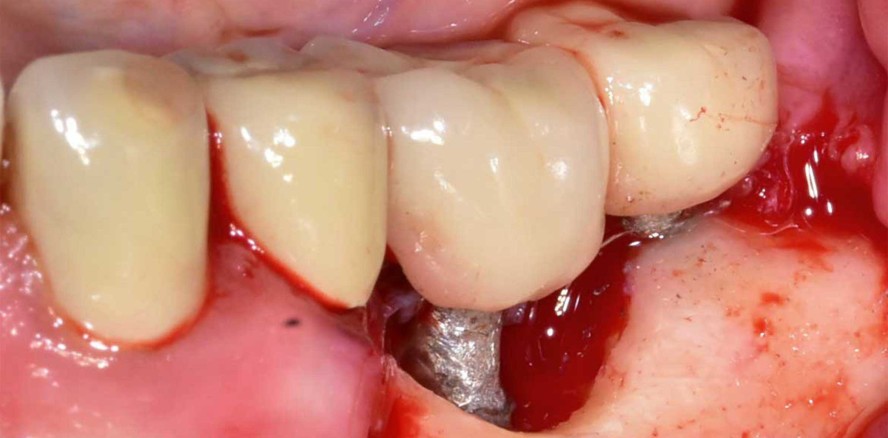

Nach eingehender Beratung und Aufklärung wurde die Patientin zur resektiven Periimplantitistherapie mittels Implantoplastik terminiert. Unter Lokalanästhesie (Articain 1:200.000) erfolgte nach streng marginaler Schnittführung (zum Erhalt der restlichen keratinisierten Mukosa) die Bildung eines Trapezlappens mit distaler Entlastung am Implantat 37 und mesialer Entlastung am Zahn 35 (Abb. 4). Nach mechanischer Dekontamination mittels Kürette wurden die freiliegenden Implantatoberflächen im Sinne einer Implantoplastik modelliert (Abb. 5). Dabei wurden die Implantatgewinde so weit abgetragen, bis eine glatte Implantatoberfläche mit geringerer Gefahr der Plaqueakkumulation und Rekontamination entstand. Bei der Implantoplastik gilt es, lediglich die Implantatwindungen zu ebnen, um nicht den Durchmesser der Implantate zu reduzieren (Frakturgefahr). Zum Abschluss wurde die Oberfläche mit einem Arkansas-Stein poliert. Der Wundverschluss erfolgte mit monofilem Nahtmaterial der Stärke 5/0 (Monofast, mectron) nach gründlicher Spülung mit CHX (Chlorhexamed forte alkoholfrei 0,2 %, GSK) und Kochsalzlösung (Abb. 6).